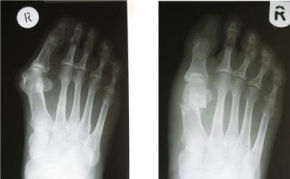

Figure 3: Pre and post Anter-posterior plain X-ray of the foot six months following Mitchell's osteotomy. View Figure 3

The mean shortening of the first metatarsal after Mitchell's osteotomy was 4 mm (2-7 mm) (Figure 3 and Table 1).